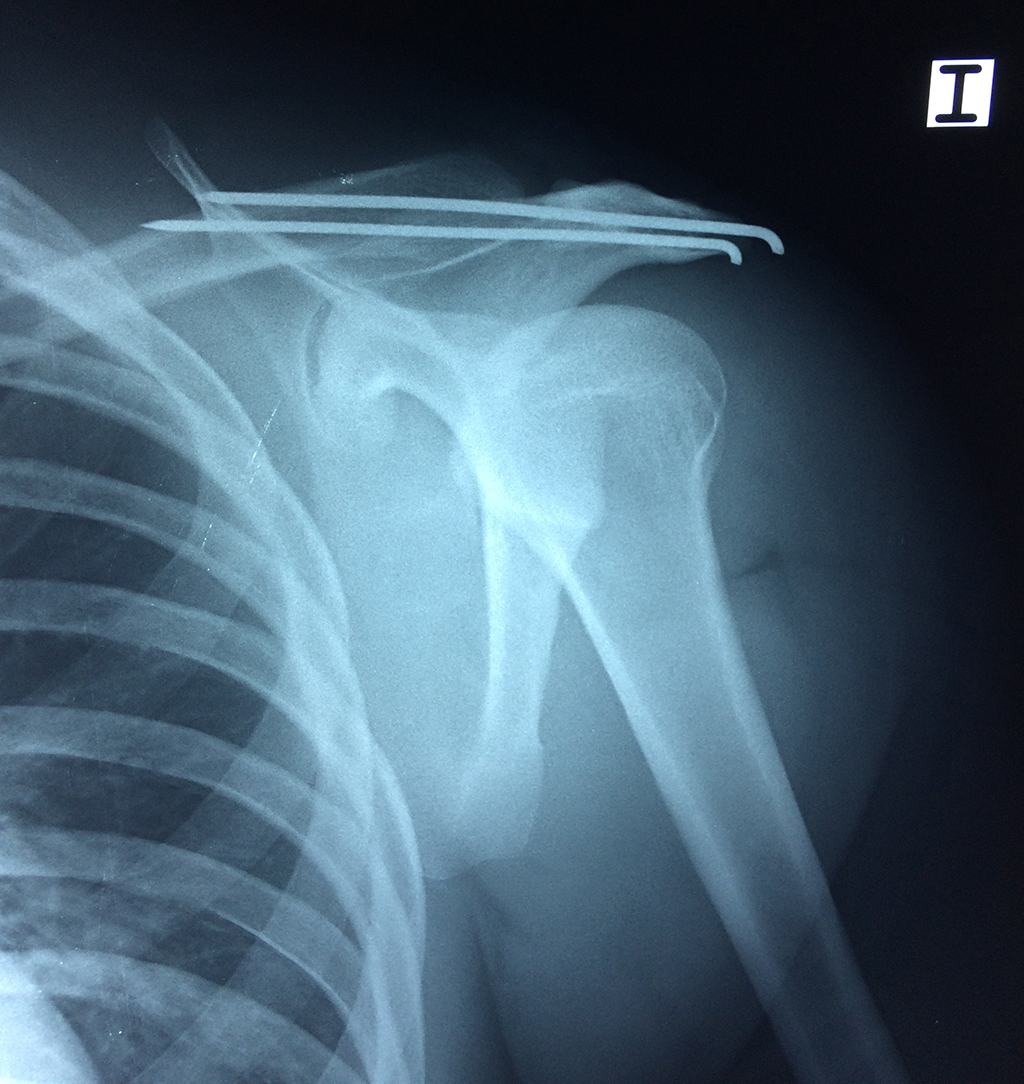

En anatomía humana, el hombro es la parte del cuerpo donde se une el brazo con el tronco. Está formado por la conjunción de los extremos de tres huesos: la clavícula, la escápula y el húmero; así como por músculos, ligamentos y tendones.

Exteriormente una envoltura de tejido blando circunda el conjunto, es la llamada cápsula articular que está reforzada por varios ligamentos que le dan estabilidad e impiden que los huesos se desplacen más allá de sus límites fisiológicos. Un conjunto de músculos y sus tendones se unen a las superficies de los huesos y hacen posible la movilidad de la articulación, entre ellos es muy importante el manguito rotador formado por cuatro músculos que proporcionan movilidad y estabilidad al hombro.